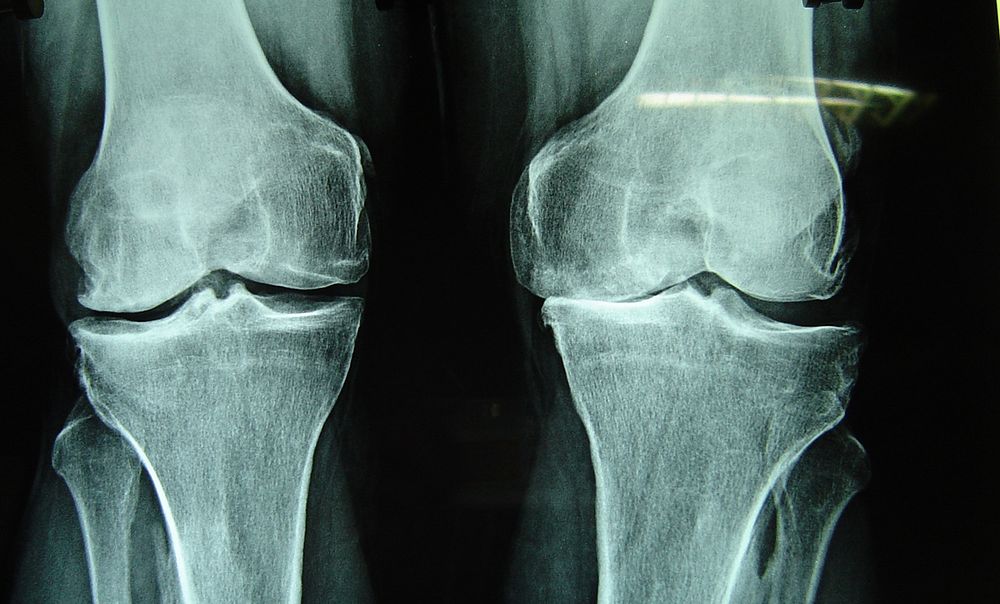

У моей дочери Анны детский церебральный паралич, она передвигалась по квартире тяжело, с трудом, на сильно согнутых ногах. В 1998 году в результате неправильного лечения (гипсования) в нашем городе девочка совсем перестала ходить – у нее сильно заболели колени, они были горячими и распухшими. Через несколько месяцев бесполезного лечения сделали снимки: остеопороз (т. е. разрушение костной ткани) коленных суставов. Доктора назначили интенсивную терапию. Анна прошла 2 долгих курса лечения в детской городской больнице. Но когда год спустя сделали повторный снимок, выяснилось, что улучшений почти не было, – ярко выраженный остеопороз. Врачи ничего утешительного сказать не могли: возможно, с возрастом кости окрепнут и болезнь пройдет, но нужны годы. А по поводу основного диагноза сказали, что ничем не могут нам помочь, и надежды на то, что когда-нибудь Анна вновь пойдет, практически нет.

После поступления в санаторий, в ходе предоперационного обследования, Анне сделали рентген тазобедренных суставов, который выявил подвывихи. Мы были в шоке: если так, девочку ожидала не планируемая мышечная, а очень сложная костная операция и год пребывания в гипсе! Снимок сделали в пятницу, а 8 апреля – это было Вербное воскресение – мы отправились в собор г. Симферополя к мощам святителя Луки, понимая, что в создавшейся ситуации помочь может только он. Мы горячо молились «благому и милостивому» врачу Луке, прося его об исцелении. Заказали ему молебен, взяли масла из лампадки у его мощей. В понедельник были сделаны повторные снимки, и они показали, что подвывихов тазобедренных суставов нет. Более того, когда был произведен рентген коленей, выяснилось, что они совершенно здоровы! «У вас нет остеопороза и, судя по всему, никогда не было», – уверенно сказала врач. И только предыдущие снимки доказывали обратное...